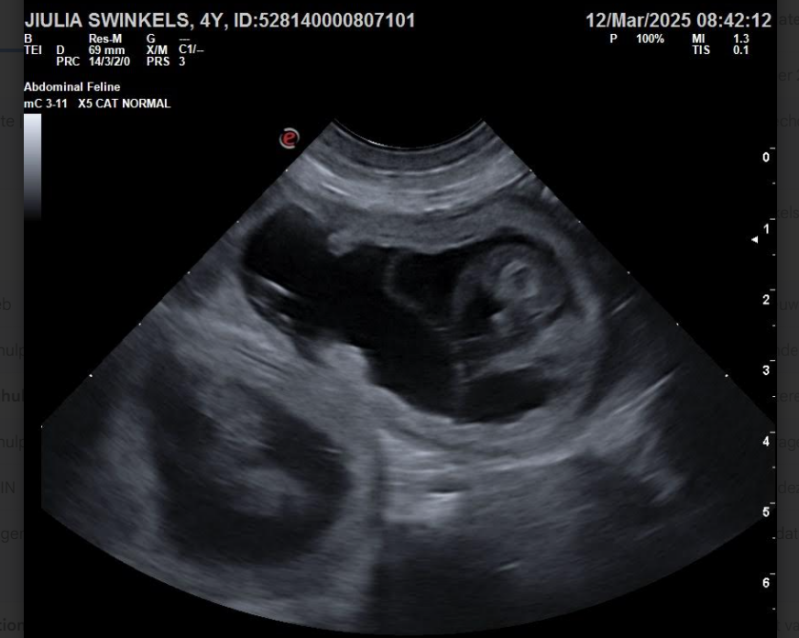

12 maart zijn we bij de dierenarts geweest om een dracht echo te maken.

Jiulia is drachtig.

Nu nog geduldig wachten en hopen dat alles goed blijft gaan voor de pups